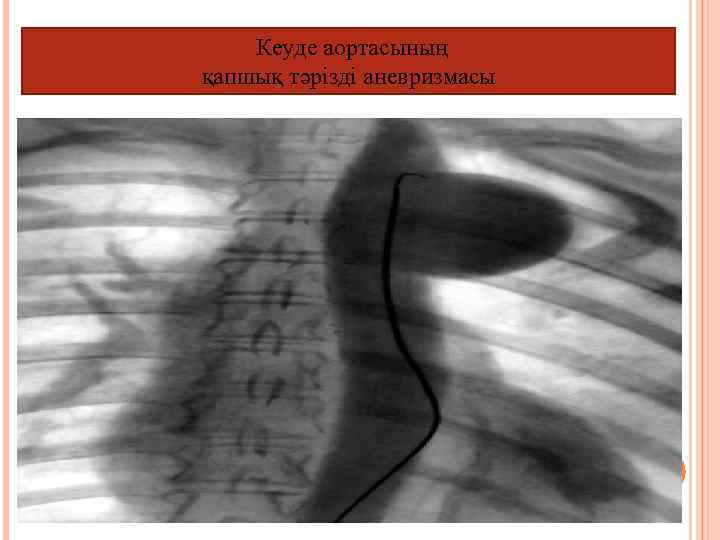

Кеуделік аортография (кеуде аортасы және оның тармақтары) Анамолия, аневризма, аорталық клапан жетіспеушілігі. Тікелей және жанама түрі бар: Тікелей, бұл кезде жамбас немесе бұғанаасты артериясын катетеризациялайды. Жанама: катетерді жамбас немесе шынтақ веналарына контрасты зат жіберіледі

Кеуде аортасының қапшық тәрізді аневризмасы